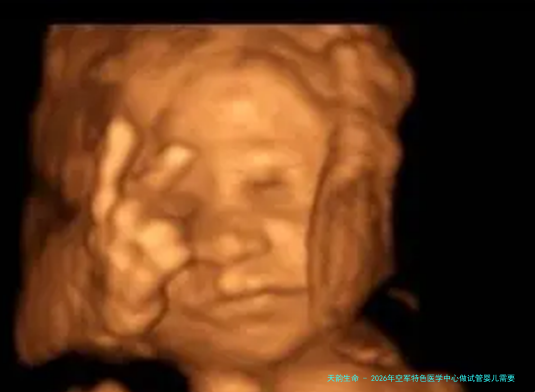

2026年,空军特色医学中心将继续致力于为军队及家属提供品质高的医护服务。在辅助生殖范畴,跟着技术的不断前行和临床经验的积聚,空军特性医学中心的试管婴儿技术已取得了显着成果,受到广阔人民的认可和信赖。那么,2026年空军特色医学中心做试管婴儿需要几许钱?详细费用在何处些项目呢?下列将为您详细解读。

2026年,空军特性医学中心试管婴儿的总花销大致在98765元左右。具体费用会根据个别情况和治疗方案有所浮动。例如,如果需要进行精卵保存等辅助技术,费用将会与之相应增加。